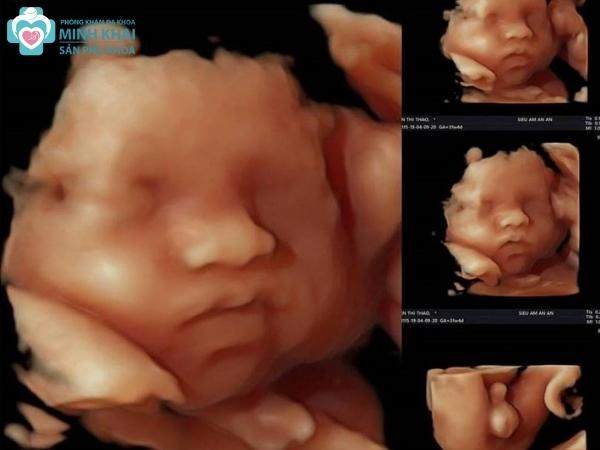

Phân tích hình ảnh siêu âm 3D trong sản khoa

Kết quả siêu âm 3D thai nhi thường có màu và rất sắc nét, nó giúp quan sát được khá nhiều góc độ của thai nhi. Do đó phân tích hình ảnh siêu âm 3D đóng vai trò quan trọng trong việc thăm khám và chẩn đoán sức khỏe thai kỳ.

Hình ảnh siêu âm 3D thai nhi tuần 12-15

Trong 3 tháng đầu thai kỳ, hình ảnh phôi thai được phương pháp siêu âm 3D thể hiện sinh động và rõ nét trong bức ảnh. Đây là khoảng thời gian em bé hiếu động nhất nên các bức ảnh 3 chiều có thể phản ánh được hoạt động của thai nhi như ngáp, dụi mắt, nắm tay,...khá rõ ràng. Ngoài ra, nó còn cho mẹ xác định vị trí mắt, mũi và miệng trên gương mặt bé nhưng chưa thể soi được cụ thể bố cục, đường nét khuôn mặt chi tiết theo từng bộ phận.

Hình ảnh siêu âm 3D thai nhi tuần 20-25

Vào thời điểm giữa thai kỳ tại tuần 20 đến 25, hình ảnh siêu âm 3D cho thấy rõ hình thái cũng như cấu tạo hộp sọ em bé. Ngoài ra những bộ phận cơ thể khác như tứ chi, khuôn mặt, tim phổi, dạ dày,.... cũng được phản ánh vô cùng chi tiết. Nhờ đó, bác sĩ có thể sớm chẩn đoán bệnh lý cũng như phát hiện khiếm khuyết bẩm sinh cho bé nhanh chóng.